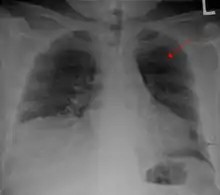

الكسر الضلعي هو كسر أو تحطم في واحد أو أكثر من العظام التي تشكل القفص الصدري. ونادراً ما يكسر الضلع الأول بسبب موقعه خلف عظم الترقوة والذي يجعله محمياً . ومع ذلك، إذا ما تم كسرها، يمكن أن تحدث أضراراً جسيمة في الضفيرة العضدية من الأعصاب والأوعية تحت الترقوة. الكسور في الضلعين الأول والثاني غالباً ما تكون مرتبطة مع إصابات في الرأس والوجه أكثر من ارتباطها بكسور في الأضلاع الأخرى. كسور الضلوع الوسطى هي الأكثر شيوعاً.[1] الكسور عادة ما تحدث من ضربات مباشرة أو غير مباشرة من إصابات السحق. أضعف جزء من الضلع هو فقط المنطقة الأمامية لزاويته، ولكن يمكن أن يحدث الكسر في أي مكان. الأضلاع الأكثر تعرضاً للكسر هي الضلع السابع والضلع العاشر. الكسور في الأضلاع السفلية قد تؤدي لمضاعفات محتملة كإصابة الحجاب الحاجز، والذي ينتج عنها فتق الحجاب الحاجز.[2] كسور الأضلاع غالباً ما تكون مؤلمة جداً لأن الأضلاع يجب أن تتحرك للسماح للتنفس. عندما يتم كسر العديد من الأضلاع في عدة أماكن ينتج عن ذلك صدر سائب، وتتحرك أجزاء العظم المنفصلة بصورة منفصلة عن باقي الصدر.

معرض صور